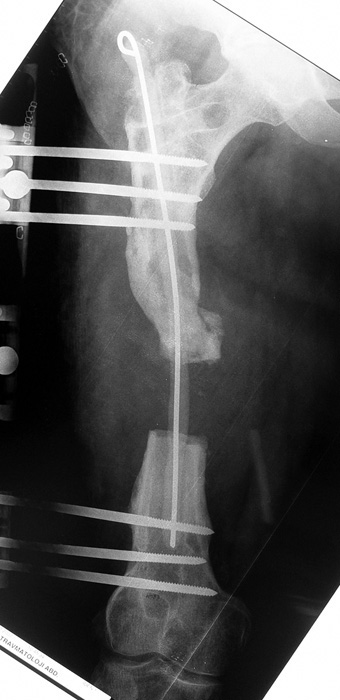

Eksternal fiksatör ile geçen süre (eksternal fiksasyon indeksi), gereken distraksiyon miktarına bağlıdır ve bu süre boyunca bazı komplikasyonlarla karşılaşılabilir. Distraksiyon dönemi sona erdikten sonra, distraksiyon süresinin iki katını aşan konsolidasyon döneminde hastalar eksternal fiksatörü zorlukla tolere edebilirler. Yeterli konsolidasyon sağlanmadan eksternal fiksatör çıkartılırsa ise kırıklar, deformite ve kısalık oluşabilir. Hastanın fiksatör ile birlikte geçirdiği sürenin azaltılması ve böylece hasta konforunun ve aktivite düzeyinin arttırılması için intramedüller çivi üzerinden uzatma yöntemi uygulanmaktadır. Bu yöntemde distraksiyon dönemi sona erdiğinde kemiğin içindeki çivi statik olarak kilitlenmekte ve eksternal fiksatör çıkartılmaktadır. Stabilizasyon intramedüller çivi tarafından sağlandıktan sonra konsolidasyon dönemi gerçekleşmektedir. Bu şekilde hem eksternal fiksatörün uzun süre kalmasından hem de erken çıkartılmasından kaynaklanan komplikasyonların önüne geçilmektedir.

Vaka 3